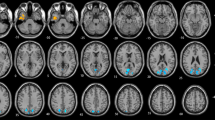

Comparing the comprehensive global topological parameters of networks between HCs and lTLE and rTLE participants (Fig. 8), the results indicate that, in the Delta, Theta, Beta, and Low Gamma bands, the global clustering coefficient (GCC) of both lTLE and rTLE subjects was significantly higher than that of HCs. In contrast, in the High Gamma band, the GCC was lower for both TLE groups compared to HC subjects. In the Alpha band, only lTLE subjects showed significantly higher GCC compared to HCs. The results for global characteristic path length (GCPL) and local efficiency (LE) were similar to those of GCC. For the LE attribute, TLE subjects had significantly higher values than HCs in the mid-to-low frequency bands (Delta, Theta, Alpha, Beta, Low Gamma), while the High Gamma band showed the opposite pattern. For the GCPL attribute, TLE subjects had significantly higher values than HCs in the mid-to-low frequencies (Delta, Beta, Low Gamma), and in the Theta band, only rTLE showed a significant difference compared to HCs. As with GCC, the High Gamma band exhibited the opposite pattern. The results for the global efficiency (GE) attribute differed from the other three attributes. In the mid frequencies (Beta, Low Gamma), TLE subjects had significantly lower GE values compared to HC subjects, while the High Gamma band showed the opposite trend.

Four global topological parameters of brain functional networks in HCs, lTLE, and rTLE patients. The SPSS Mann-Whitney U test with Holm correction was used to assess significant differences between HCs and the rTLE and lTLE groups, where * indicates \(q < 0.05\), ** indicates \(q < 0.01\), and *** indicates \(q < 0.001\).